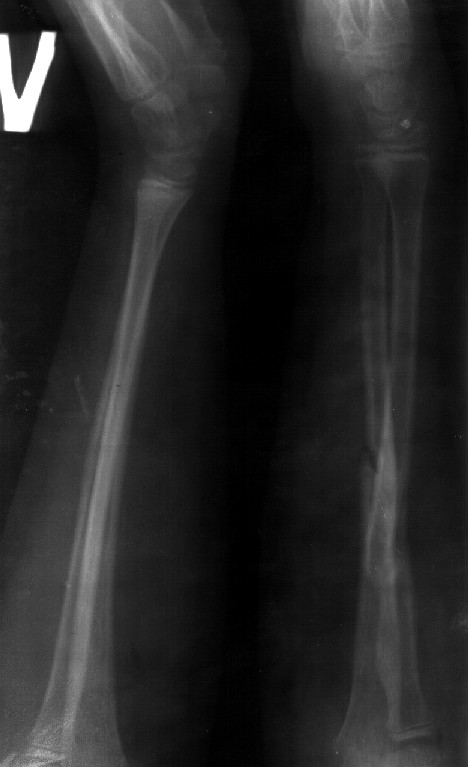

Сделал симметричные снимки с максимальной супинацией и пронацией при согнутом предплечье в 90 град. Объем ротационных движений 90-100 град.

Снимок один сделан с супинацией, второй - оба предплечья в одинаково нейтральном положении. то есть по этим снимкам объем ротационных движений не оценить. Снимко в двух проекциях лучше и делать в среднем положении между пронацией и супинацией, то есть обе проекции в однм и том же положении, когда линия, проходящая через шиловидные отростки, идет в плоскости головки. Прошу прощения за усложнение простых вещей.

А для оценки ротации лучше сделать фото - дать пациенту зажать в кулаки одинаковые палочки (телескопы от апп. Илизарова идеальны), поставить... Впрочем, вот фото, чтобы все было понятно без слов. Локти к бокам пусть остаются прижатыми не только при супинации, но и при пронации.